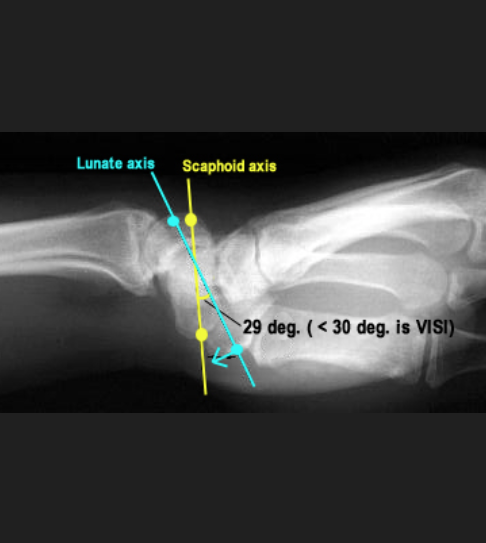

When the Lunotriquetral ligament is disrupted the scaphoid’s influence on lunate position is unchecked and the lunate gradually flexes with the scaphoid.

This leads to volar intercalated semental instability (VISI)

Normal is on average 47 degrees.

Visi is the < 30 degrees

Volar aspect of lunotriquetral ligment stronger. Dorsal side of SL ligament stronger.